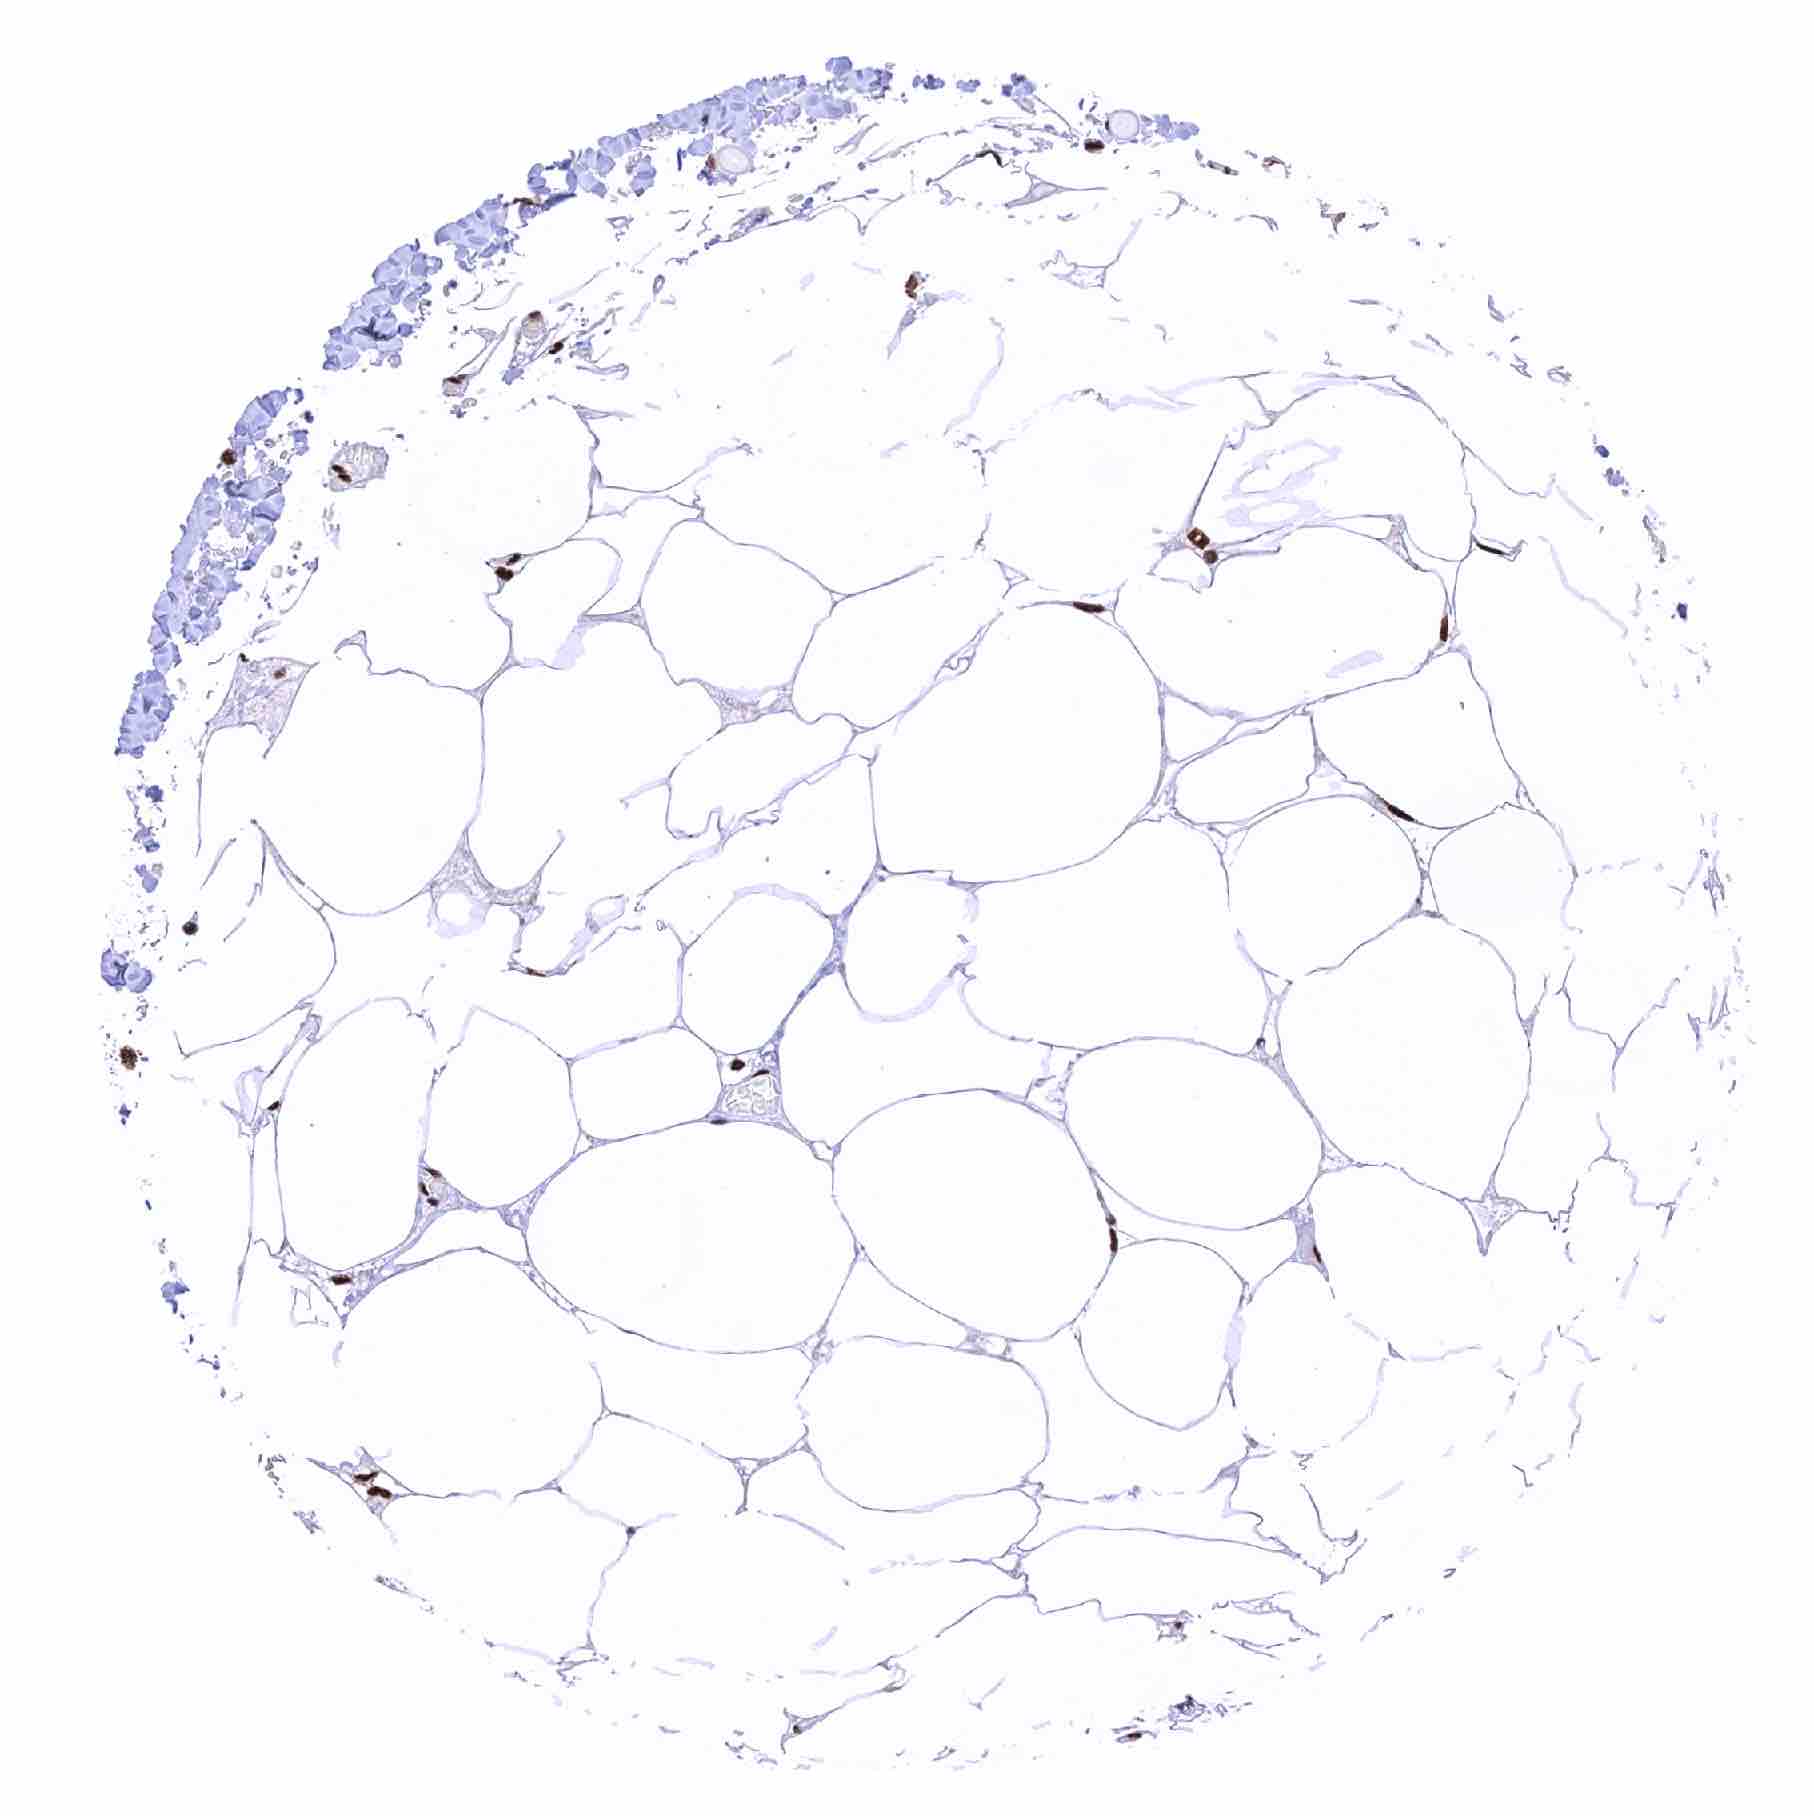

Fat